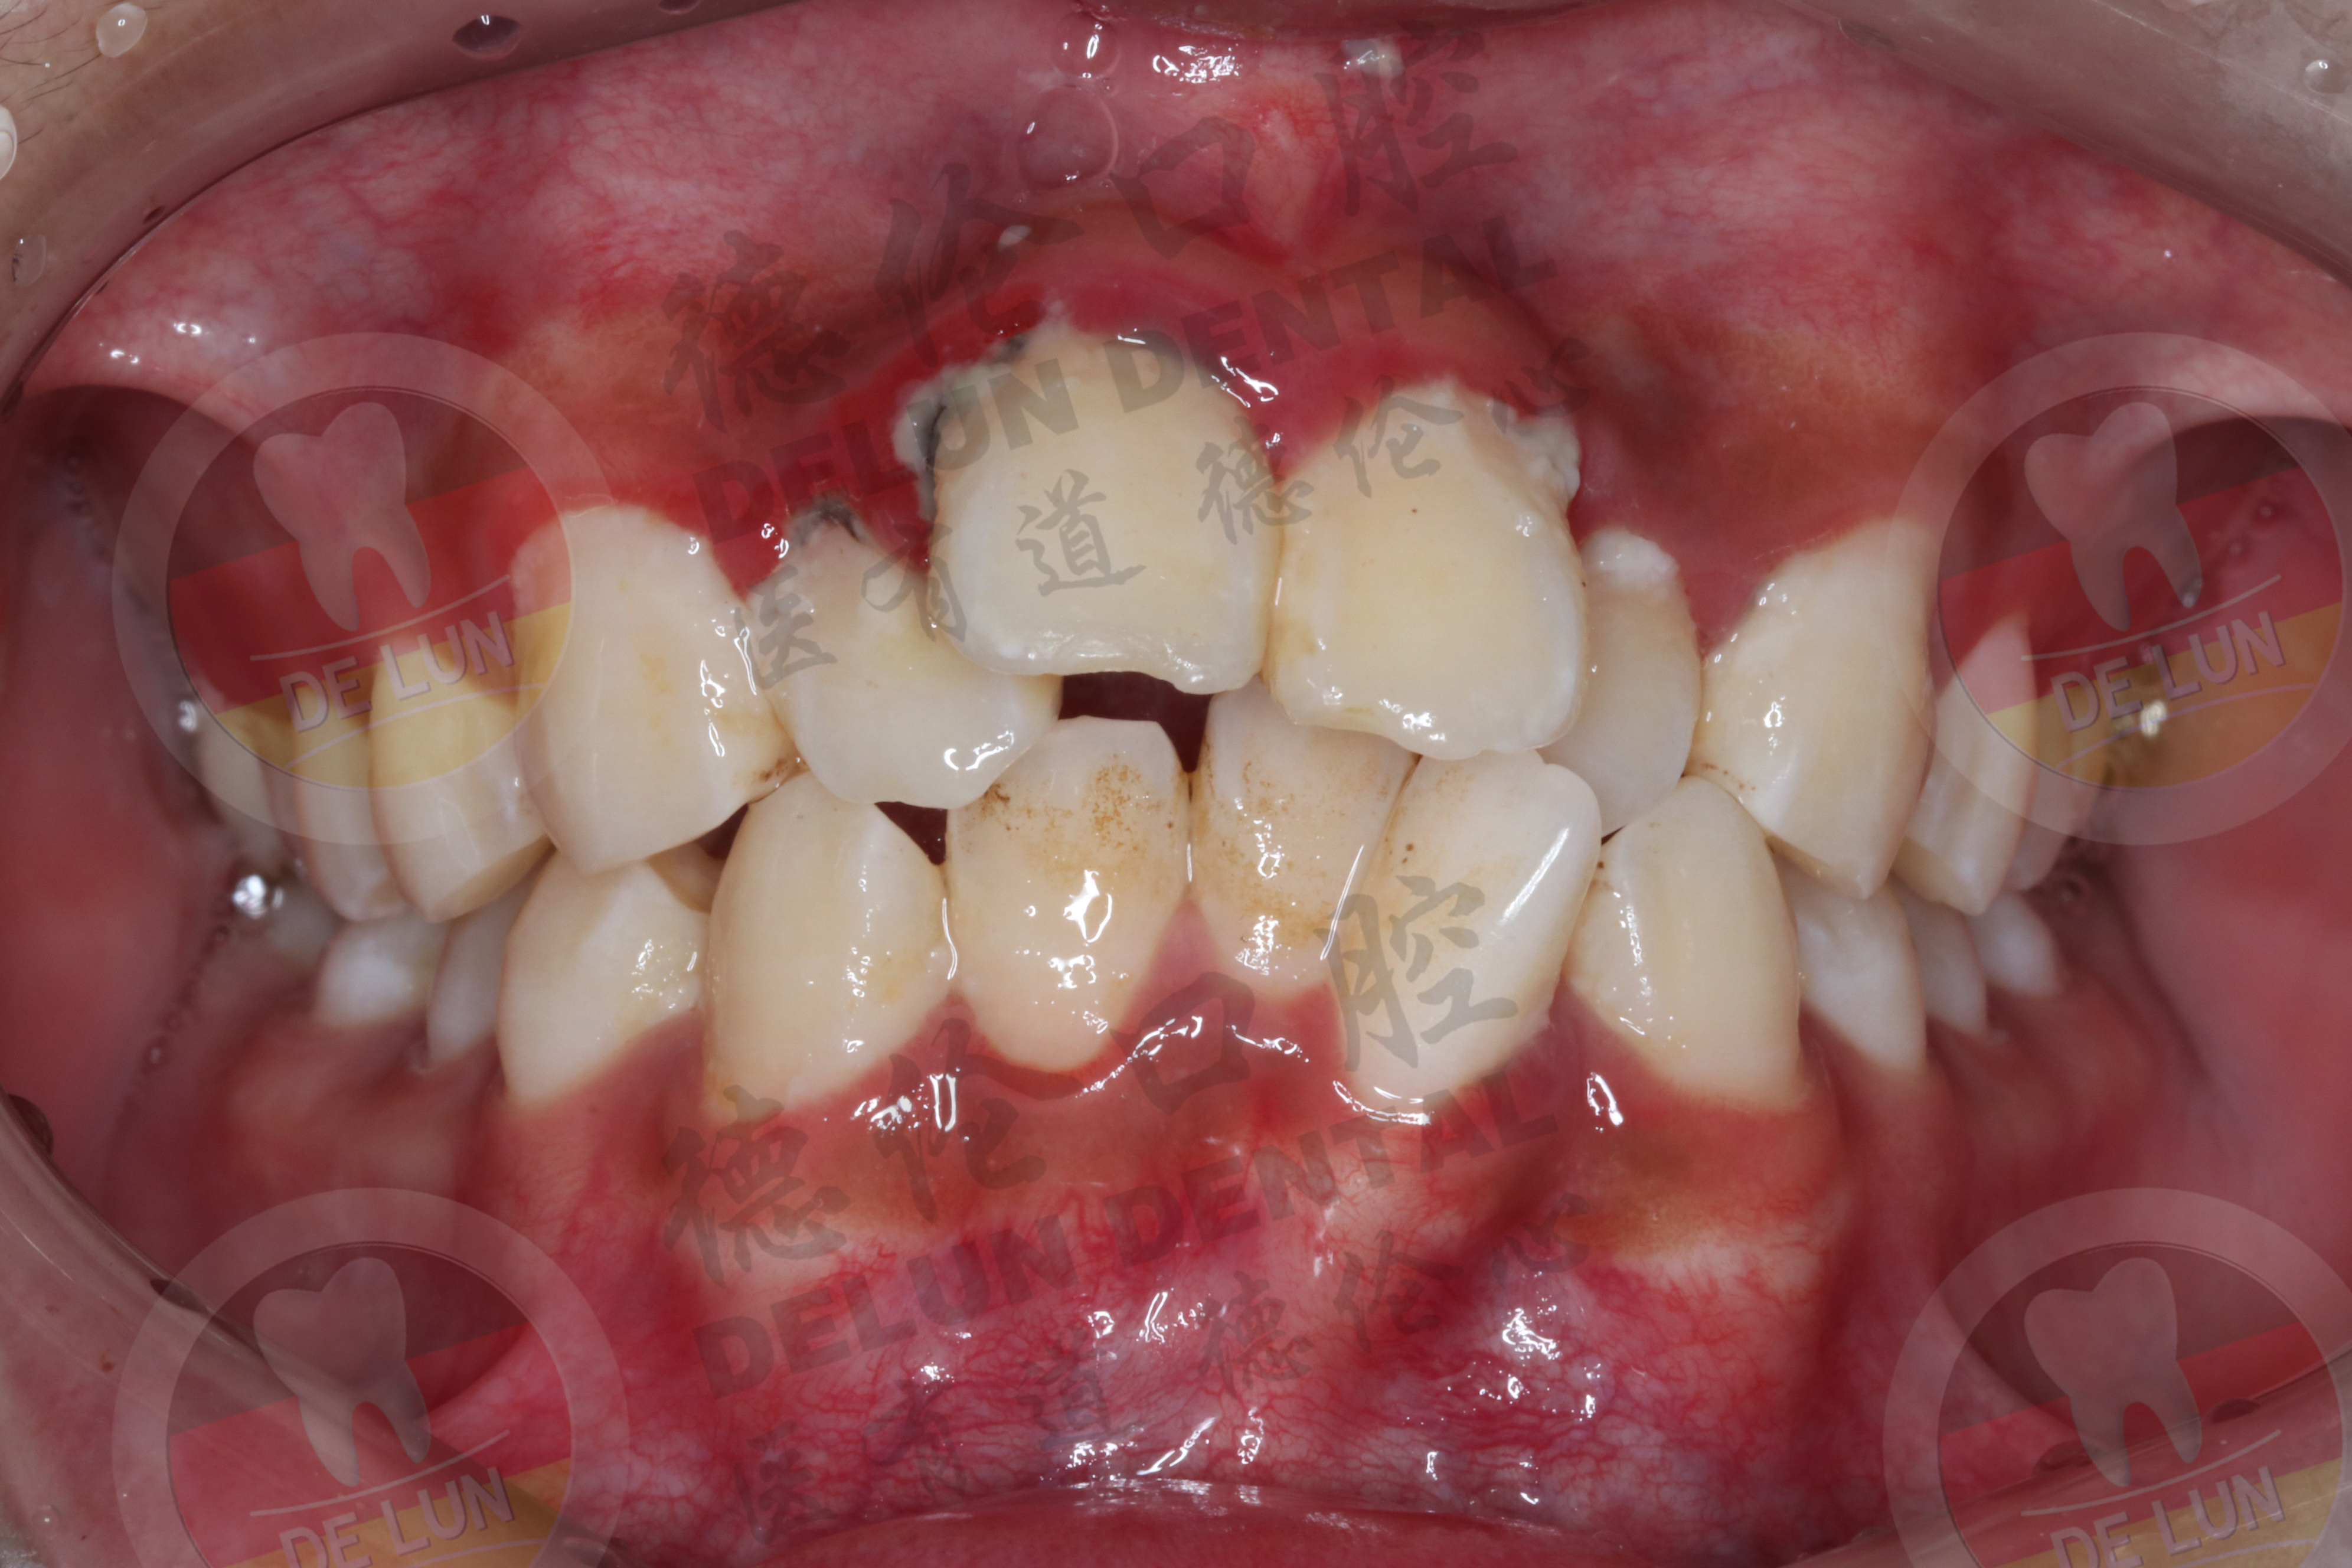

现在的人多多少少都会有牙齿不齐的情况,而牙齿拥挤也是十分常见的,像多生牙、乳牙早失等都是造成牙齿拥挤的主要原因。牙齿拥挤对患者的口腔影响非常大,不但会影响整体的口腔清洁,还会影响外观,所以应该及时进行矫正。有很多朋友对牙齿拥挤矫正的相关情况不太清楚,今天就来跟大家聊一聊,希望对各位有帮助。